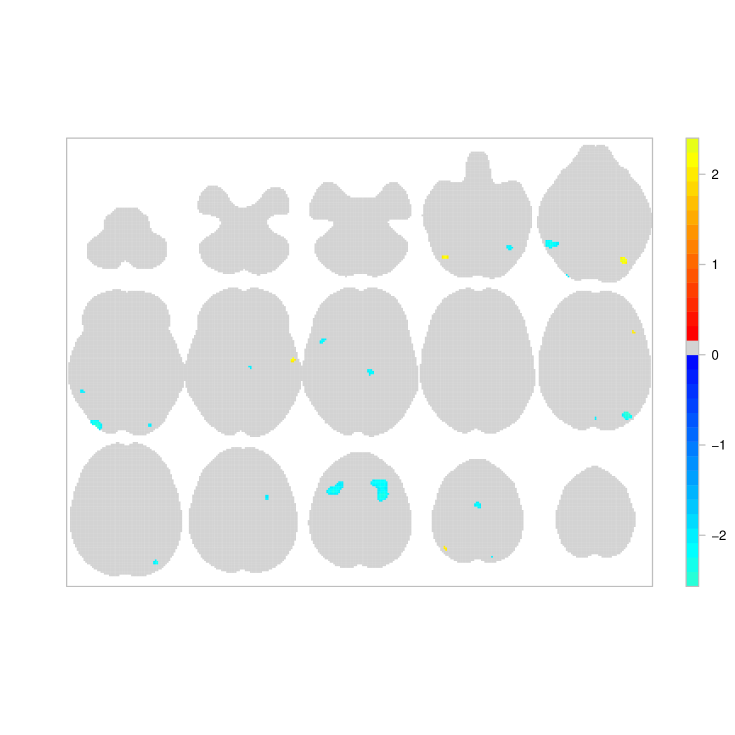

Our results provide evidence that age has an important effect on the function of working memory. The point estimate for the overall age effect is -0.22 (95% CI [-0.337,-0.120]) thus suggesting that we expect a decrease of 20% in the total number of reported activations per study, each time the average age of the participants increases by 10.99 years. Localised age effects can be identified through the posterior distribution of , the mean of which is shown in Figure 4. The map represents the multiplicative effect that an increase of the average participant age by 10.99 years has on the intensity of both verbal and non-verbal studies. Large negative age effects can be found near the left putamen ( and , middle), the insular cortex (, left) and near the superior parietal lobule ( and , right). A positive age effect is found near the precentral gyrus (, left). However, due to the limited number of studies, the posterior variance of these estimates is large in some regions of the brain, see Figure 14 of Appendix C.

Application of our model on a meta-analysis of working memory studies have given valuable insights regarding the data. While our maps for the overall pattern of WM activations (Fig. 2) and the differential effect of verbal vs. non-verbal WM tasks (Fig. 3) reflect previous findings found by Rottschy et al. (2012), our fully Bayesian approach allowed us to make direct inference on probability of any foci and expected number of foci. Our model found no regions with evidence of different rates of foci between verbal and non-verbal WM tasks (Appendix C, Table LABEL:tab:fullbrain2). Importantly, our model allows a meta-regression, and we examined the effect of age and found no strong effects but generally negative effects of age on the number of foci.